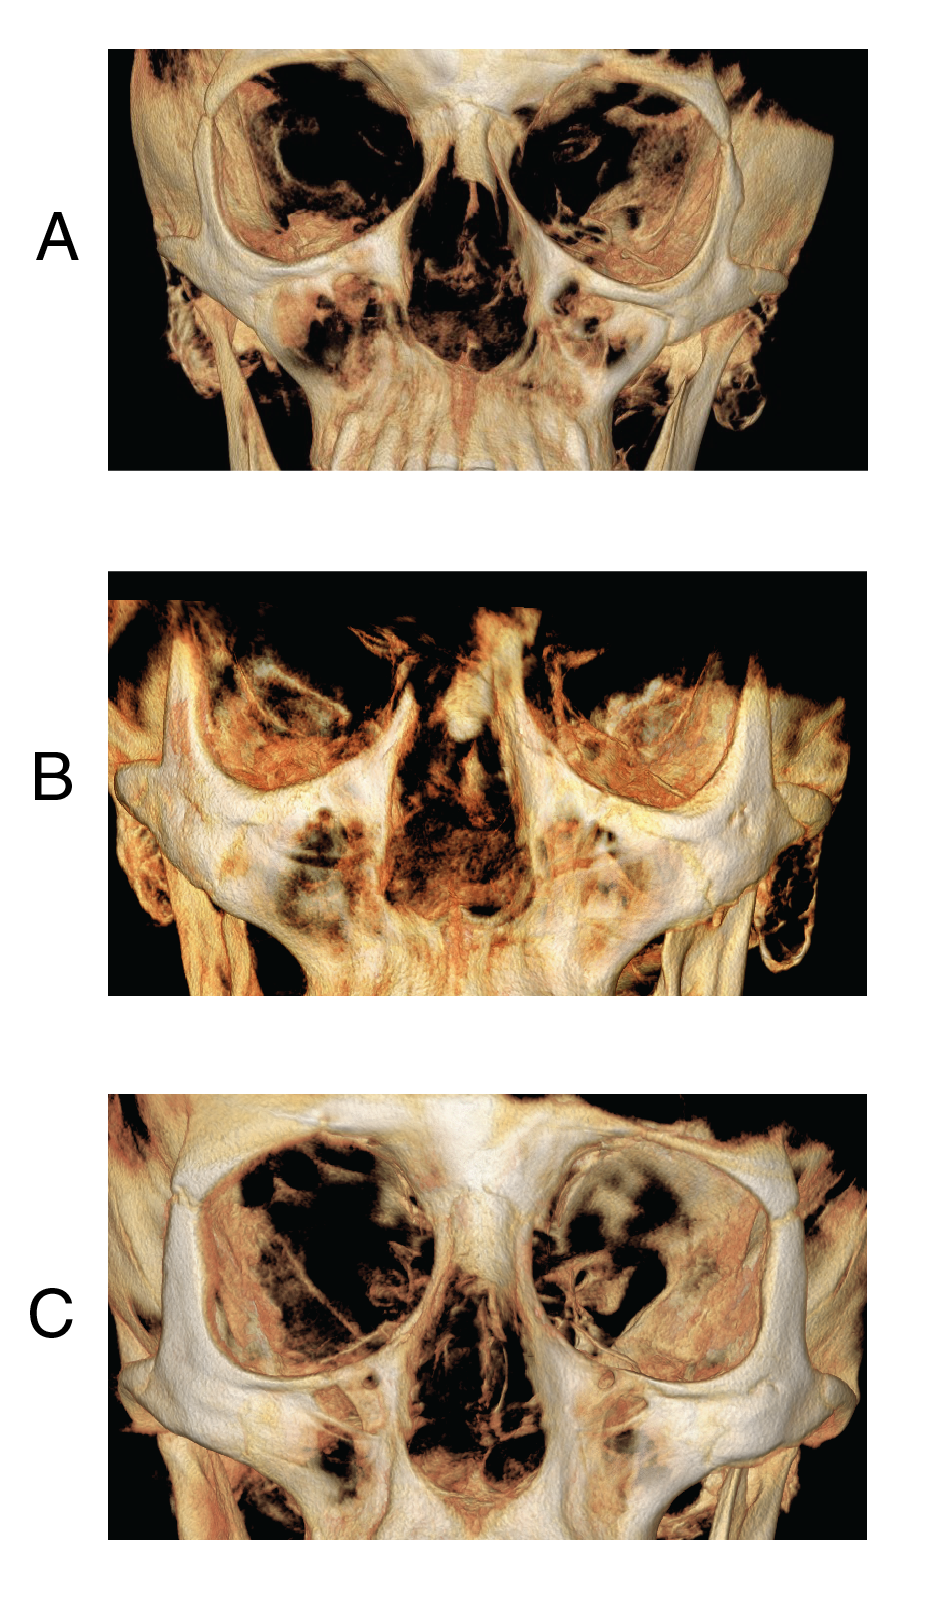

Figure 7: Zygomatic bone in NM patients. 3D CBCT reconstruction of the (A) NM patient, (B) matched open bite patient, and (C) matched control patient. The orbital rim, zygoma, and maxilla body demonstrate thinner cortical bone and more porosity.